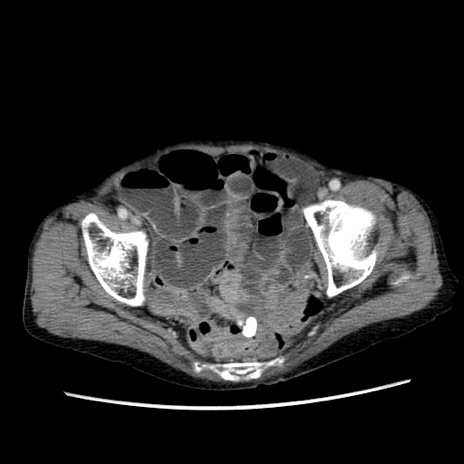

症例25(横断像)

【症例】80歳代女性

【主訴】胸のつかえ感

【現病歴】約9時間前に食後から胸のつかえた感じあり、嘔吐あり、来院。

【既往歴】胃癌(全摘)、胆摘、虫垂炎

【身体所見】心窩部に圧痛あり、反跳痛なし。

【データ】WBC 5700、CRP 0.05